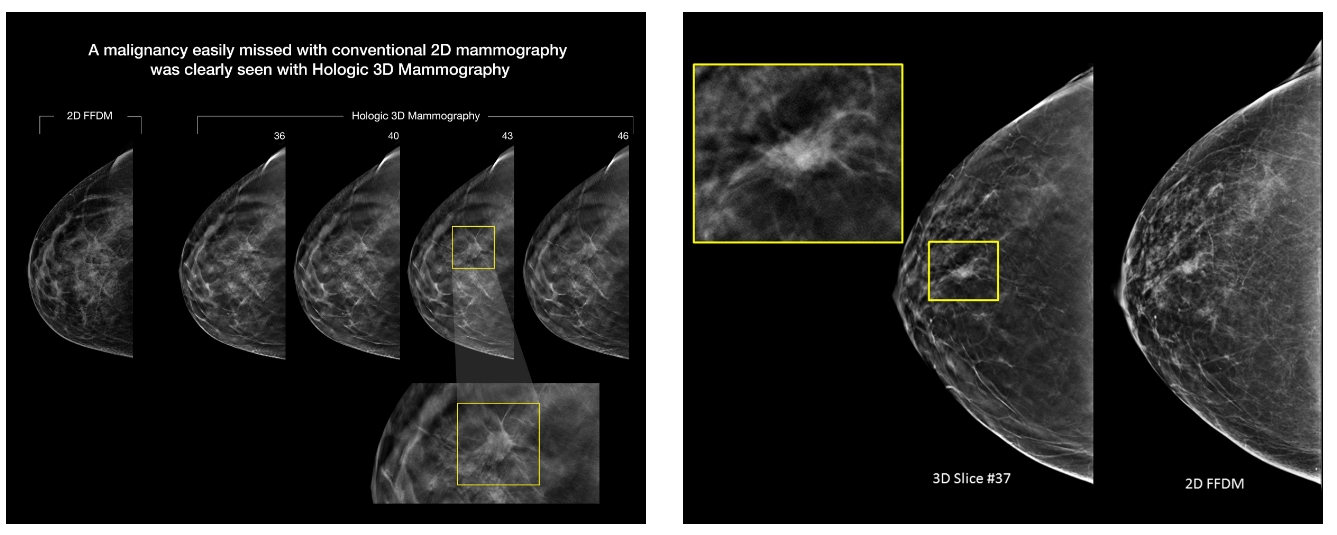

توضیحات تصاویر: در تصویر بالا مشاهده می‌شود که ضایعه‌ی بدخیم پستان، در ماموگرافی دوبعدی (2D FFDM) به‌راحتی پنهان مانده، اما در برش‌های متوالی ماموگرافی سه‌بعدی Hologic (3D Tomosynthesis) به‌وضوح قابل مشاهده است. این فناوری با حذف هم‌پوشانی بافت‌ها، قدرت تشخیص ضایعات اولیه را تا ۴۰٪ افزایش می‌دهد.

این دستگاه، که از دقیق‌ترین و به‌روزترین فناوری‌های تصویربرداری پستان در جهان محسوب می‌شود، قادر است با وضوحی بسیار بالا و از زوایای مختلف،  ضایعات احتمالی پستان را در مراحل اولیه شناسایی کند. برخلاف ماموگرافی‌های دوبعدی ، در تکنولوژی توموسنتز سه‌بعدی، بافت‌های روی‌هم‌افتاده از یکدیگر تفکیک شده و پزشک می‌تواند با دقتی بی‌نظیر، تفاوت بین بافت‌های سالم و توده‌های مشکوک را تشخیص دهد.